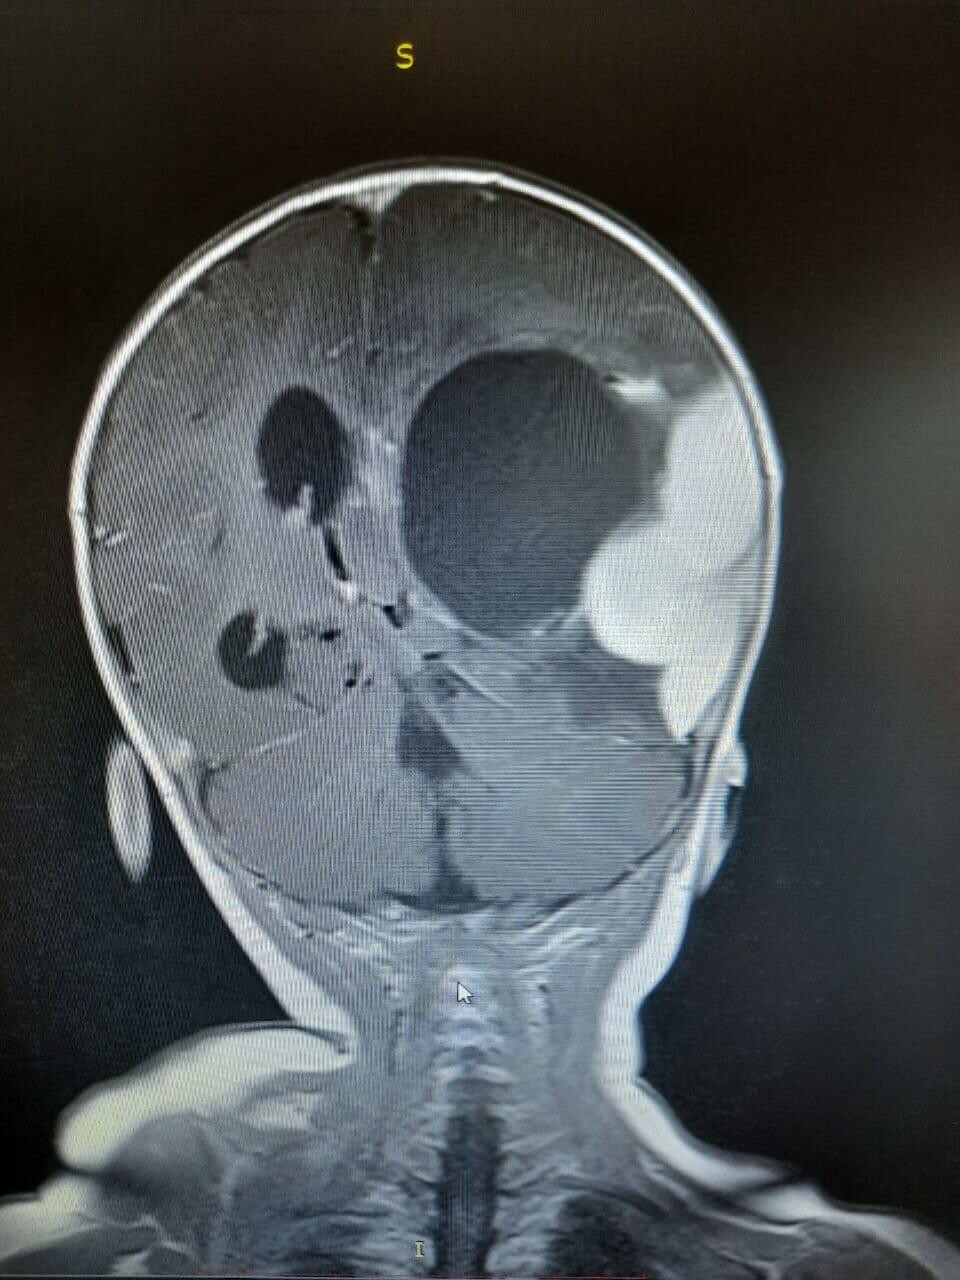

Как распознать опухоль головного мозга на УЗИ